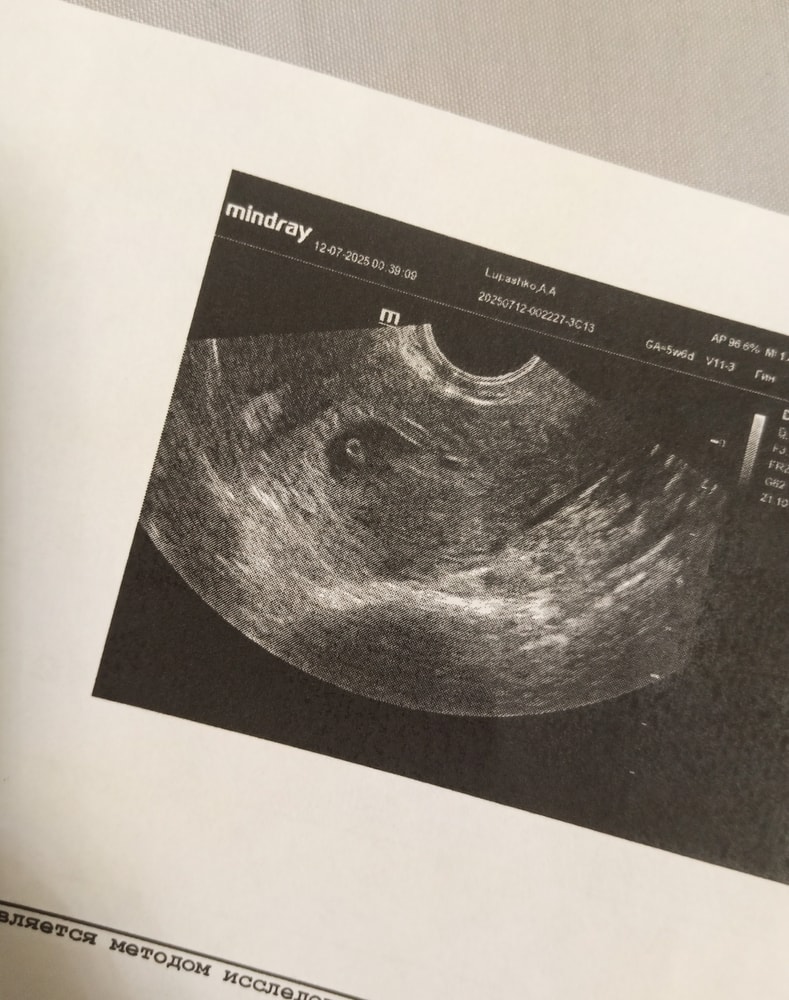

Сходила девочки на узи

Моя беременность

С.б + 108 ударов в минуту

Дай бог чтобы дальше все было хорошо